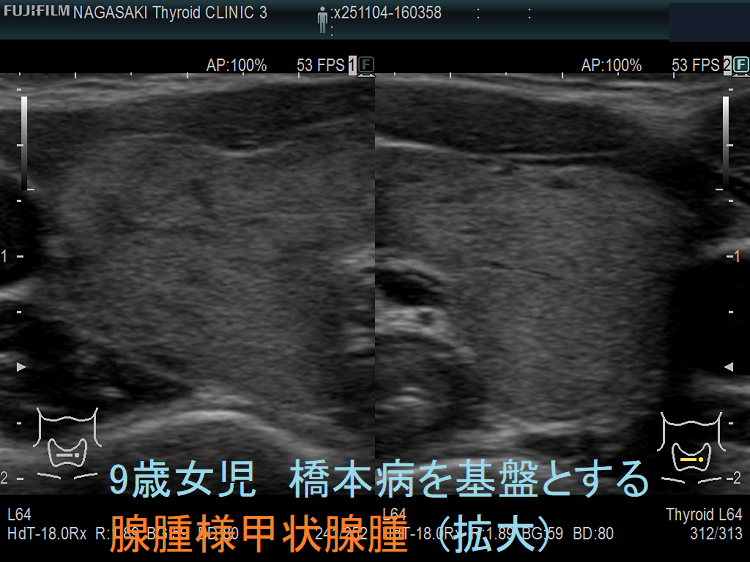

成人と同じく、小児にも橋本病を基盤とする腺腫様甲状腺腫が存在します。最も、橋本病の罹病期間は、大人と比べて遥かに短いため、腺腫様甲状腺腫にまで発展するケースは少ない。下記は、成長障害から甲状腺機能低下症と、橋本病を基盤とする腺腫様甲状腺腫が見つかった9歳女児のケースです。